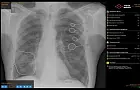

Ранее министр здравоохранения региона Айрат Рахматуллин заявил, что искусственный интеллект используется для анализа лучевых исследований в более чем 50 медицинских учреждениях Башкирии.

По его словам, развитие комплексных решений на базе ИИ является приоритетным. Сейчас технологии способны выявлять до 14 типов патологий при компьютерной томографии органов грудной клетки. Среди новых возможностей – диагностика пневмоторакса, изменений в подмышечных лимфоузлах, переломов рёбер, а также признаков пневмонии, плеврита, патологий надпочечников и позвоночника.

Кроме того, ИИ активно используется для анализа изменений в лимфатических узлах. При обнаружении проблемной зоны система её подсвечивает, и врач уже сопоставляет информацию с клинической картиной и результатами обследования. Это помогает выявлять заболевания без плана и начинать лечение на более ранних стадиях.

В будущем планируется расширение функционала сервисов, включая модули для аналитики бронхоэктазов, фиброзов и эмфиземы легких.